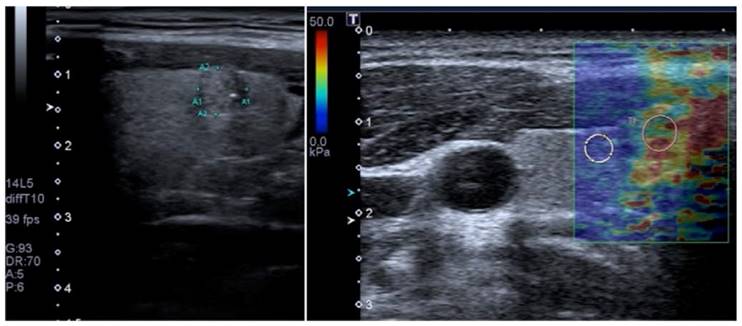

In SWI, a quantitative measure of the shear wave velocity (m/sec) or Young's modulus (kPa) in a lesion is obtained either as a single value in a small fixed region of interest (ROI) or for each pixel in a field of view (FOV) box displayed as a color map [19, 67]. Usually, a color scale ranging from 0 (dark blue = soft) to 180kPa (red=hard) is used in breast USE [73] (Figure 7).

Figure 7

Side-by-side display of anatomical B-mode US image (left) and overlaid color map of simultaneous shear wave measurements (right) of a breast lesion obtained with 2D-SWE on a SuperSonic Imagine (SSI) AixplorerTM. In this system, red color represents stiff tissue and blue color reflects soft tissue. The suspicious hypoechoic lesion (shown within rectangle on B-mode image) has an irregular border, angular margins, is slightly wider than tall and shows posterior acoustic shadowing. The elastogram suggested malignant etiology due to increased stiffness (red/yellow/green) and ductal adenocarcinoma was confirmed on subsequent biopsy. Image courtesy by Dr. Osmar Saito.

Theranostics Image